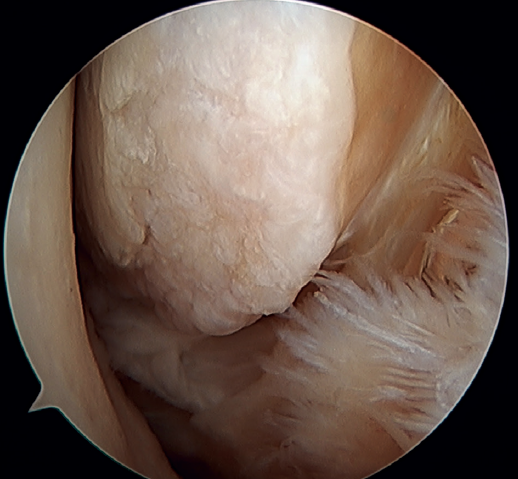

A recent consensus(64) recommends reconstruction of the ATFL and CFL (Figures 5 and 6) in cases of generalized laxity or when there is poor tissue quality. Other indications would be when there are doubts about subtalar stability or in patients with a ruptured CFL. For some authors, BMI > 30 kg/m2 would also be an indication for this technique.

Figure 5. Tearing of the anterior talofibular ligament and calcaneofibular ligament with poor tissue quality of the ligament remnant.

Figure 6. Arthroscopic view of a dual allograft reconstruction of the anterior talofibular ligament (1) and the calcaneofibular ligament (2), showing correct tension and positioning of the fascicles.